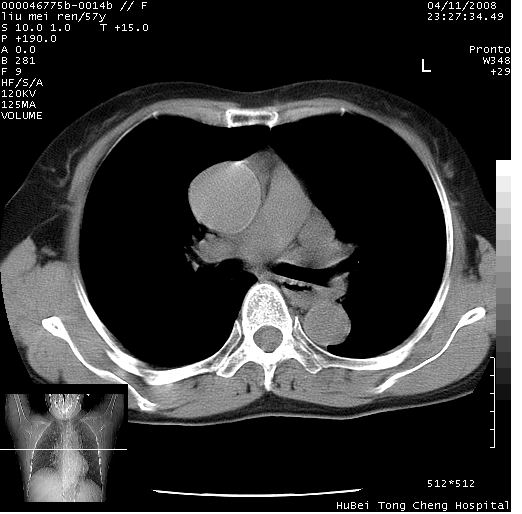

标题: CT12948:鉴赏一下——上腔静脉变异(CT平扫表现)。

患者 女,57岁。因车祸受伤,其家属要求行“全身ct检查”。平素健康。

胸部ct轴位平扫(层厚10mm,螺距1.5,重建间隔10mm),图像如下:

左位上腔静脉,先天变异。